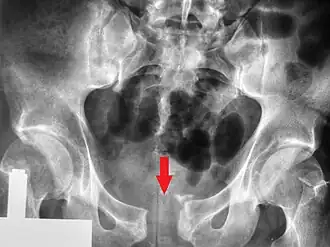

Una radiografía pélvica que muestra una fractura de libro abierto | ||

En medicina se denomina fractura de pelvis a un tipo de fractura que afecta a la pelvis ósea. La pelvis es una estructura compleja formada por la unión de varios huesos, la fractura puede afectar al hueso sacro, el ilion, el isquion, el acetábulo o el hueso pubis. La causa más frecuente en personas de edad avanzada es caída accidental, en personas jóvenes son secundarias a impactos de gran intensidad como accidentes de tráfico o caídas de altura.[1]